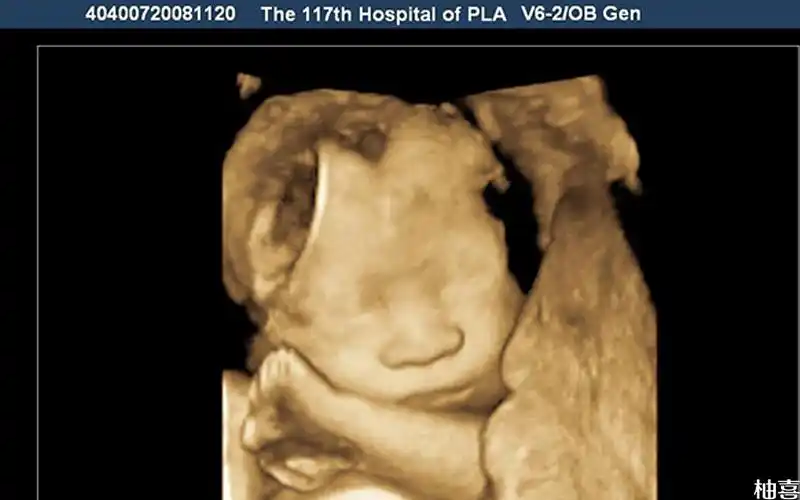

做胎儿大排畸检查到底是选三维好还是四维好详细对比超明白

三维平安归来,女宝宝一枚

孕中期三维彩超顺利通过,接健康宝宝

三维彩超